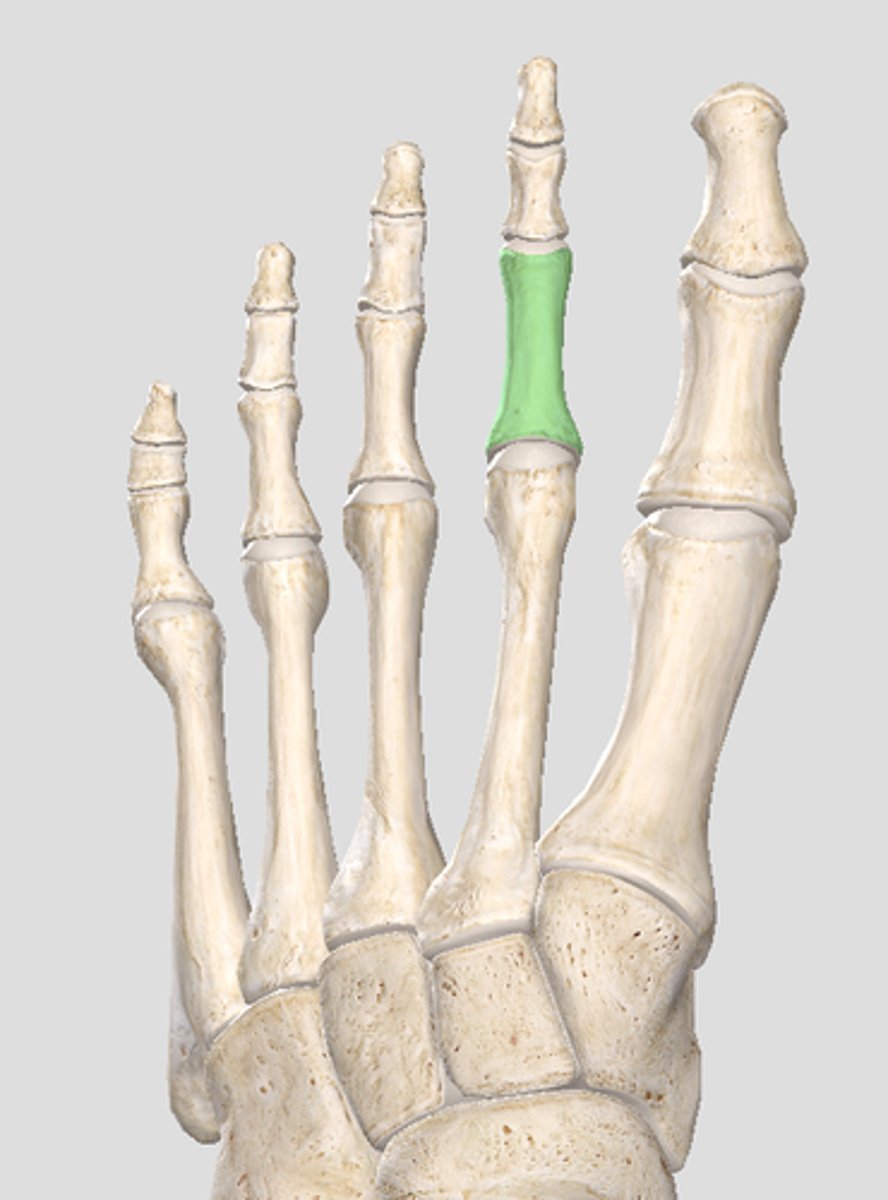

Middle phalanx of digit 4